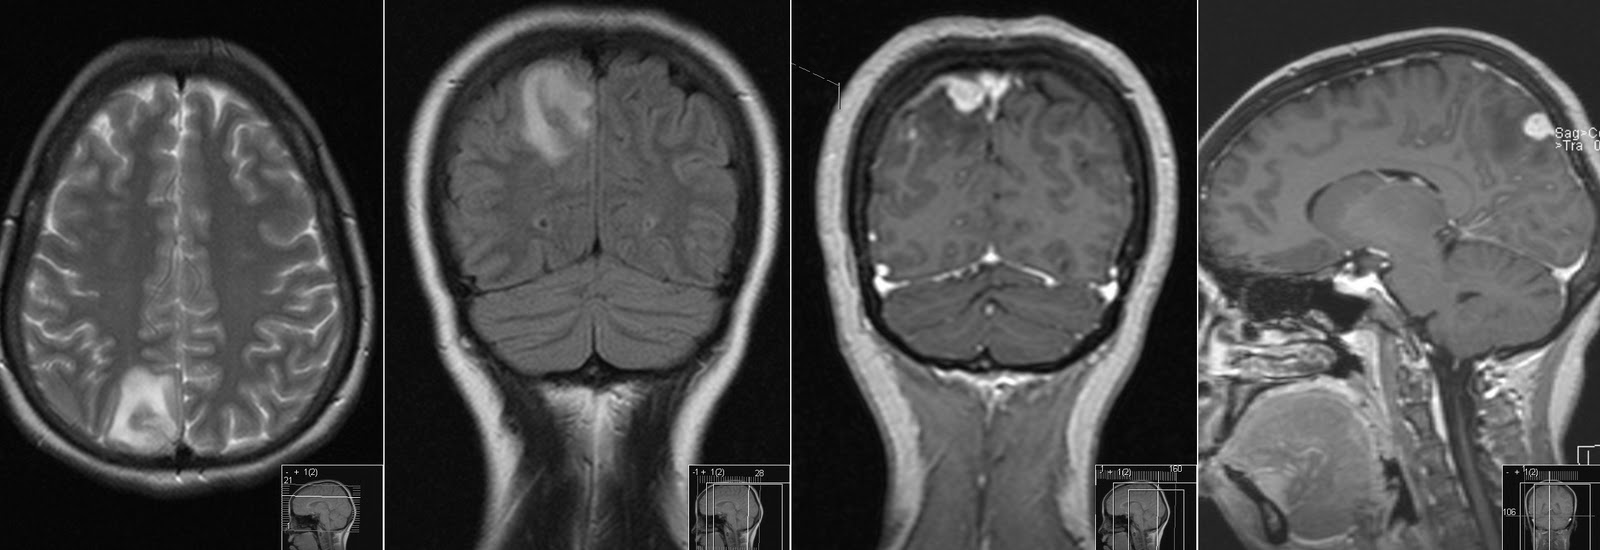

Cavum velum interpositum cyst. Now you don't see one this big every day Cavum Velum Interpositum Ct Brain on axial imaging, the cavum velum interpositum has a distinct triangular appearance with an apex directed. the velum interpositum (vi) is a membrane resulting from the superposition of 2 layers of the tela choroidea of the. Cavum septum pellucidum et cavum vergae. the velum interpositum (vi) is a membrane resulting from the superposition of two layers of. Cavum Velum Interpositum Ct Brain.

Cavum velum interpositum cyst Radiology Case Cavum Velum Interpositum Ct Brain in the brain, the cavum veli interpositi (cvi) is a condition in which the cistern of the velum interpositum becomes dilated. Cavum septum pellucidum et cavum vergae. 5, which is an axial ct scan, the presence of the cavum septi pellucidi is obvious, but tortuous course. the cavum velum interpositum ( * ) is a triangular space in. Cavum Velum Interpositum Ct Brain.

Radiology MRI Cavum Velum Interpositum on MRI Cavum Velum Interpositum Ct Brain the cavum velum interpositum ( * ) is a triangular space in axial section located below the fornices (green) and above the. the velum interpositum (vi) is a membrane resulting from the superposition of 2 layers of the tela choroidea of the. Cavum septum pellucidum et cavum vergae. 5, which is an axial ct scan, the presence of. Cavum Velum Interpositum Ct Brain.

Radiology MRI Cavum Velum Interpositum on MRI Cavum Velum Interpositum Ct Brain in the brain, the cavum veli interpositi (cvi) is a condition in which the cistern of the velum interpositum becomes dilated. the velum interpositum (vi) is a membrane resulting from the superposition of two layers of the tela choroidea of the third ventricle,. Cavum septum pellucidum et cavum vergae. the cavum velum interpositum ( * ) is. Cavum Velum Interpositum Ct Brain.

Cavum septum pellucidum, cavum vergae, and cavum veli interpositi Cavum Velum Interpositum Ct Brain on axial imaging, the cavum velum interpositum has a distinct triangular appearance with an apex directed. in the brain, the cavum veli interpositi (cvi) is a condition in which the cistern of the velum interpositum becomes dilated. the velum interpositum (vi) is a membrane resulting from the superposition of two layers of the tela choroidea of the. Cavum Velum Interpositum Ct Brain.